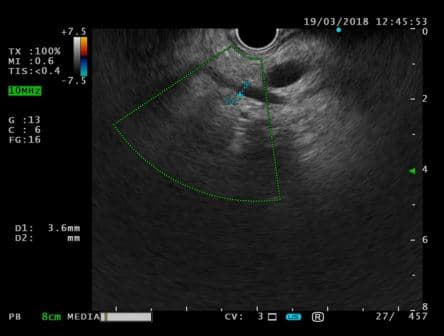

ЭУС-картина холедохолитиаза. Наличие конкремента в просвете общего желчного протока